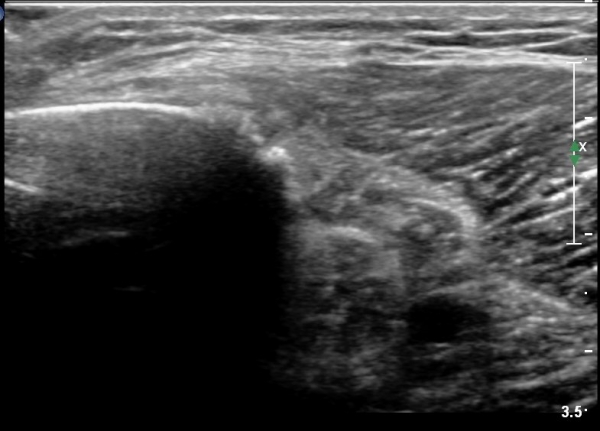

[¹«¸­] °æ°ñ ÇǷΰñÀý ÃÊÀ½ÆÄ¼Ò°ß(sonographic findings of stress fracture of tibia)

¿ìÃø ¹ß¸ñ°ú ¾Æ·§´Ù¸® ÅëÁõ(±â°£ 2ÁÖ)

±º´ë¿¡ ÀÔ´ëÇÏ¿© ÈÆ·ÃÀ» ¹ÞÀº º´·ÂÀÌ Àִ ȯÀÚ´Â ¾à 2ÁÖ ÀüºÎÅÍ ¹ß¸ñ ºÎÀ§ÀÇ ÅëÁõÀÌ ÀÖ´ø Áß

ÃÖ±Ù¿¡´Â ¹ß¸ñ À§ ¾Æ·§´Ù¸®¿¡ ÅëÁõÀÌ ¹ß»ýÇÏ°í ½ÉÇÏ°Ô °ÉÀ¸¸é ½ÉÇØÁö´Â ¾ç»óÀÓ

¾Æ·§´Ù¸® Áß°£ ºÎÀ§¿¡ °æ¹ÌÇÑ ¿¬ºÎÁ¶Á÷ ºÎÁ¾ÀÌ °üÂûµÇ°í ¾à°£ÀÇ ±¹¼ÒÀû ¾ÐÅëÀ» º¸ÀÓ.

ÃÊÀ½ÆÄ °Ë»ç